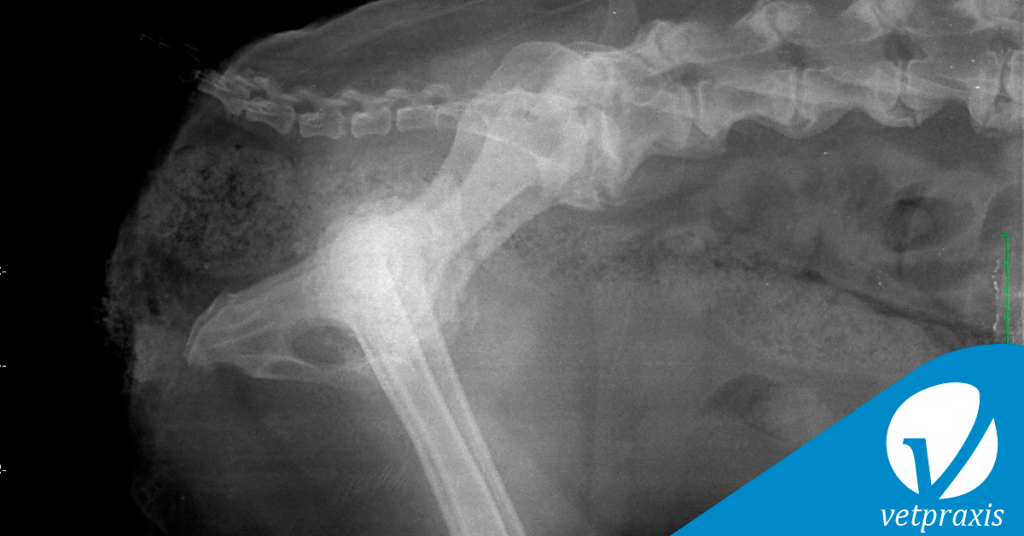

Paciente canino, 12 años, dolor agudo coxofemoral combinado con agresividad a la manipulación

Se adjuntan proyecciones L-L y V-D de columna lumbosacra, pelvis y abdomen caudal.

Respecto a los radiodiagnósticos, podemos afinar que el paciente cursa con:

I. Displasia de cadera

II. Inestabilidad lumbosacra

III. Proceso agresivo coxofemoral

IV. Vértebra transicional